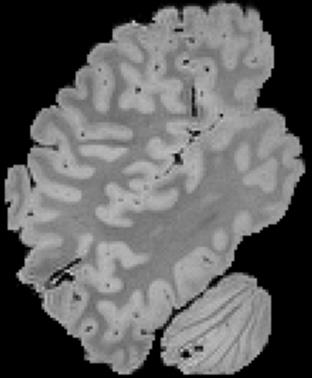

In neuroimaging, MRI tissue properties characterize underlying neurobiology, provide quantitative biomarkers for neurological disease detection and analysis, and can be used to synthesize arbitrary MRI contrasts. Estimating tissue properties from a single scan session using a protocol available on all clinical scanners promises to reduce scan time and cost, enable quantitative analysis in routine clinical scans and provide scan-independent biomarkers of disease. However, existing tissue properties estimation methods - most often $\mathbf{T_1}$ relaxation, $\mathbf{T_2^*}$ relaxation, and proton density ($\mathbf{PD}$) - require data from multiple scan sessions and cannot estimate all properties from a single clinically available MRI protocol such as the multiecho MRI scan. In addition, the widespread use of non-standard acquisition parameters across clinical imaging sites require estimation methods that can generalize across varying scanner parameters. However, existing learning methods are acquisition protocol specific and cannot estimate from heterogenous clinical data from different imaging sites. In this work we propose an unsupervised deep-learning strategy that employs MRI physics to estimate all three tissue properties from a single multiecho MRI scan session, and generalizes across varying acquisition parameters. The proposed strategy optimizes accurate synthesis of new MRI contrasts from estimated latent tissue properties, enabling unsupervised training, we also employ random acquisition parameters during training to achieve acquisition generalization. We provide the first demonstration of estimating all tissue properties from a single multiecho scan session. We demonstrate improved accuracy and generalizability for tissue property estimation and MRI synthesis.